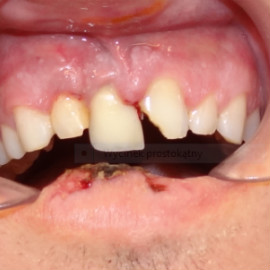

Implantacja natychmiastowa. Zęby paradontyczne. Usuniete zgodnie z popularną obecnie na zachodzie techniką: usuń zęby zanim zaniknie kość. Wynikiem takiego postępowania jest mniejsza trauma dla pacjenta i krótszy okres trwania rehabilitacji protetycznej, niższe całkowite koszty leczenia. Ale jednocześnie więcej implantów i mniej własnych zębów. W długotrwałym okresie obserwacji takie podejście daje dobre wyniki.